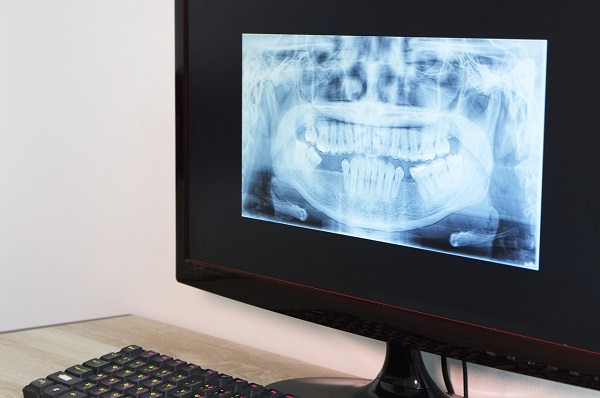

第一步:進行全面的術前檢查

這是精準預測時間的前提。必須拍攝口腔CBCT,由醫生評估您的牙槽骨三維形態、密度,並製定個性化方案。